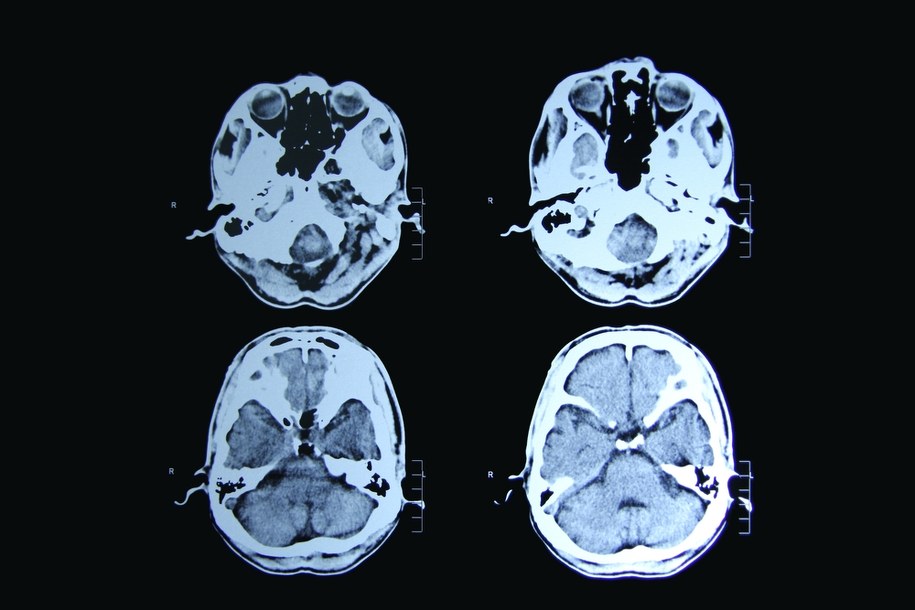

Choroba Huntingtona (pląsawica Huntingtona) to dziedziczne schorzenie, które prowadzi do stopniowego obumierania komórek nerwowych w mózgu. Objawy pojawiają się zwykle w wieku 30-40 lat, a choroba jest śmiertelna w ciągu dwóch dekad. Nowa terapia polega na wprowadzeniu do mózgu zmodyfikowanego wirusa, który dostarcza fragment DNA wyciszający produkcję toksycznego białka huntingtyny.

Pląsawica prowadzi do nieodwracalnych zmian w mózgu. Objawy przypominają połączenie chorób Parkinsona i Alzheimera - tak zwane ruchy pląsawicze, otępienie i zmiany osobowości. Dotychczas nie było terapii, która mogłaby skutecznie pomóc pacjentom - leczono tylko objawy.